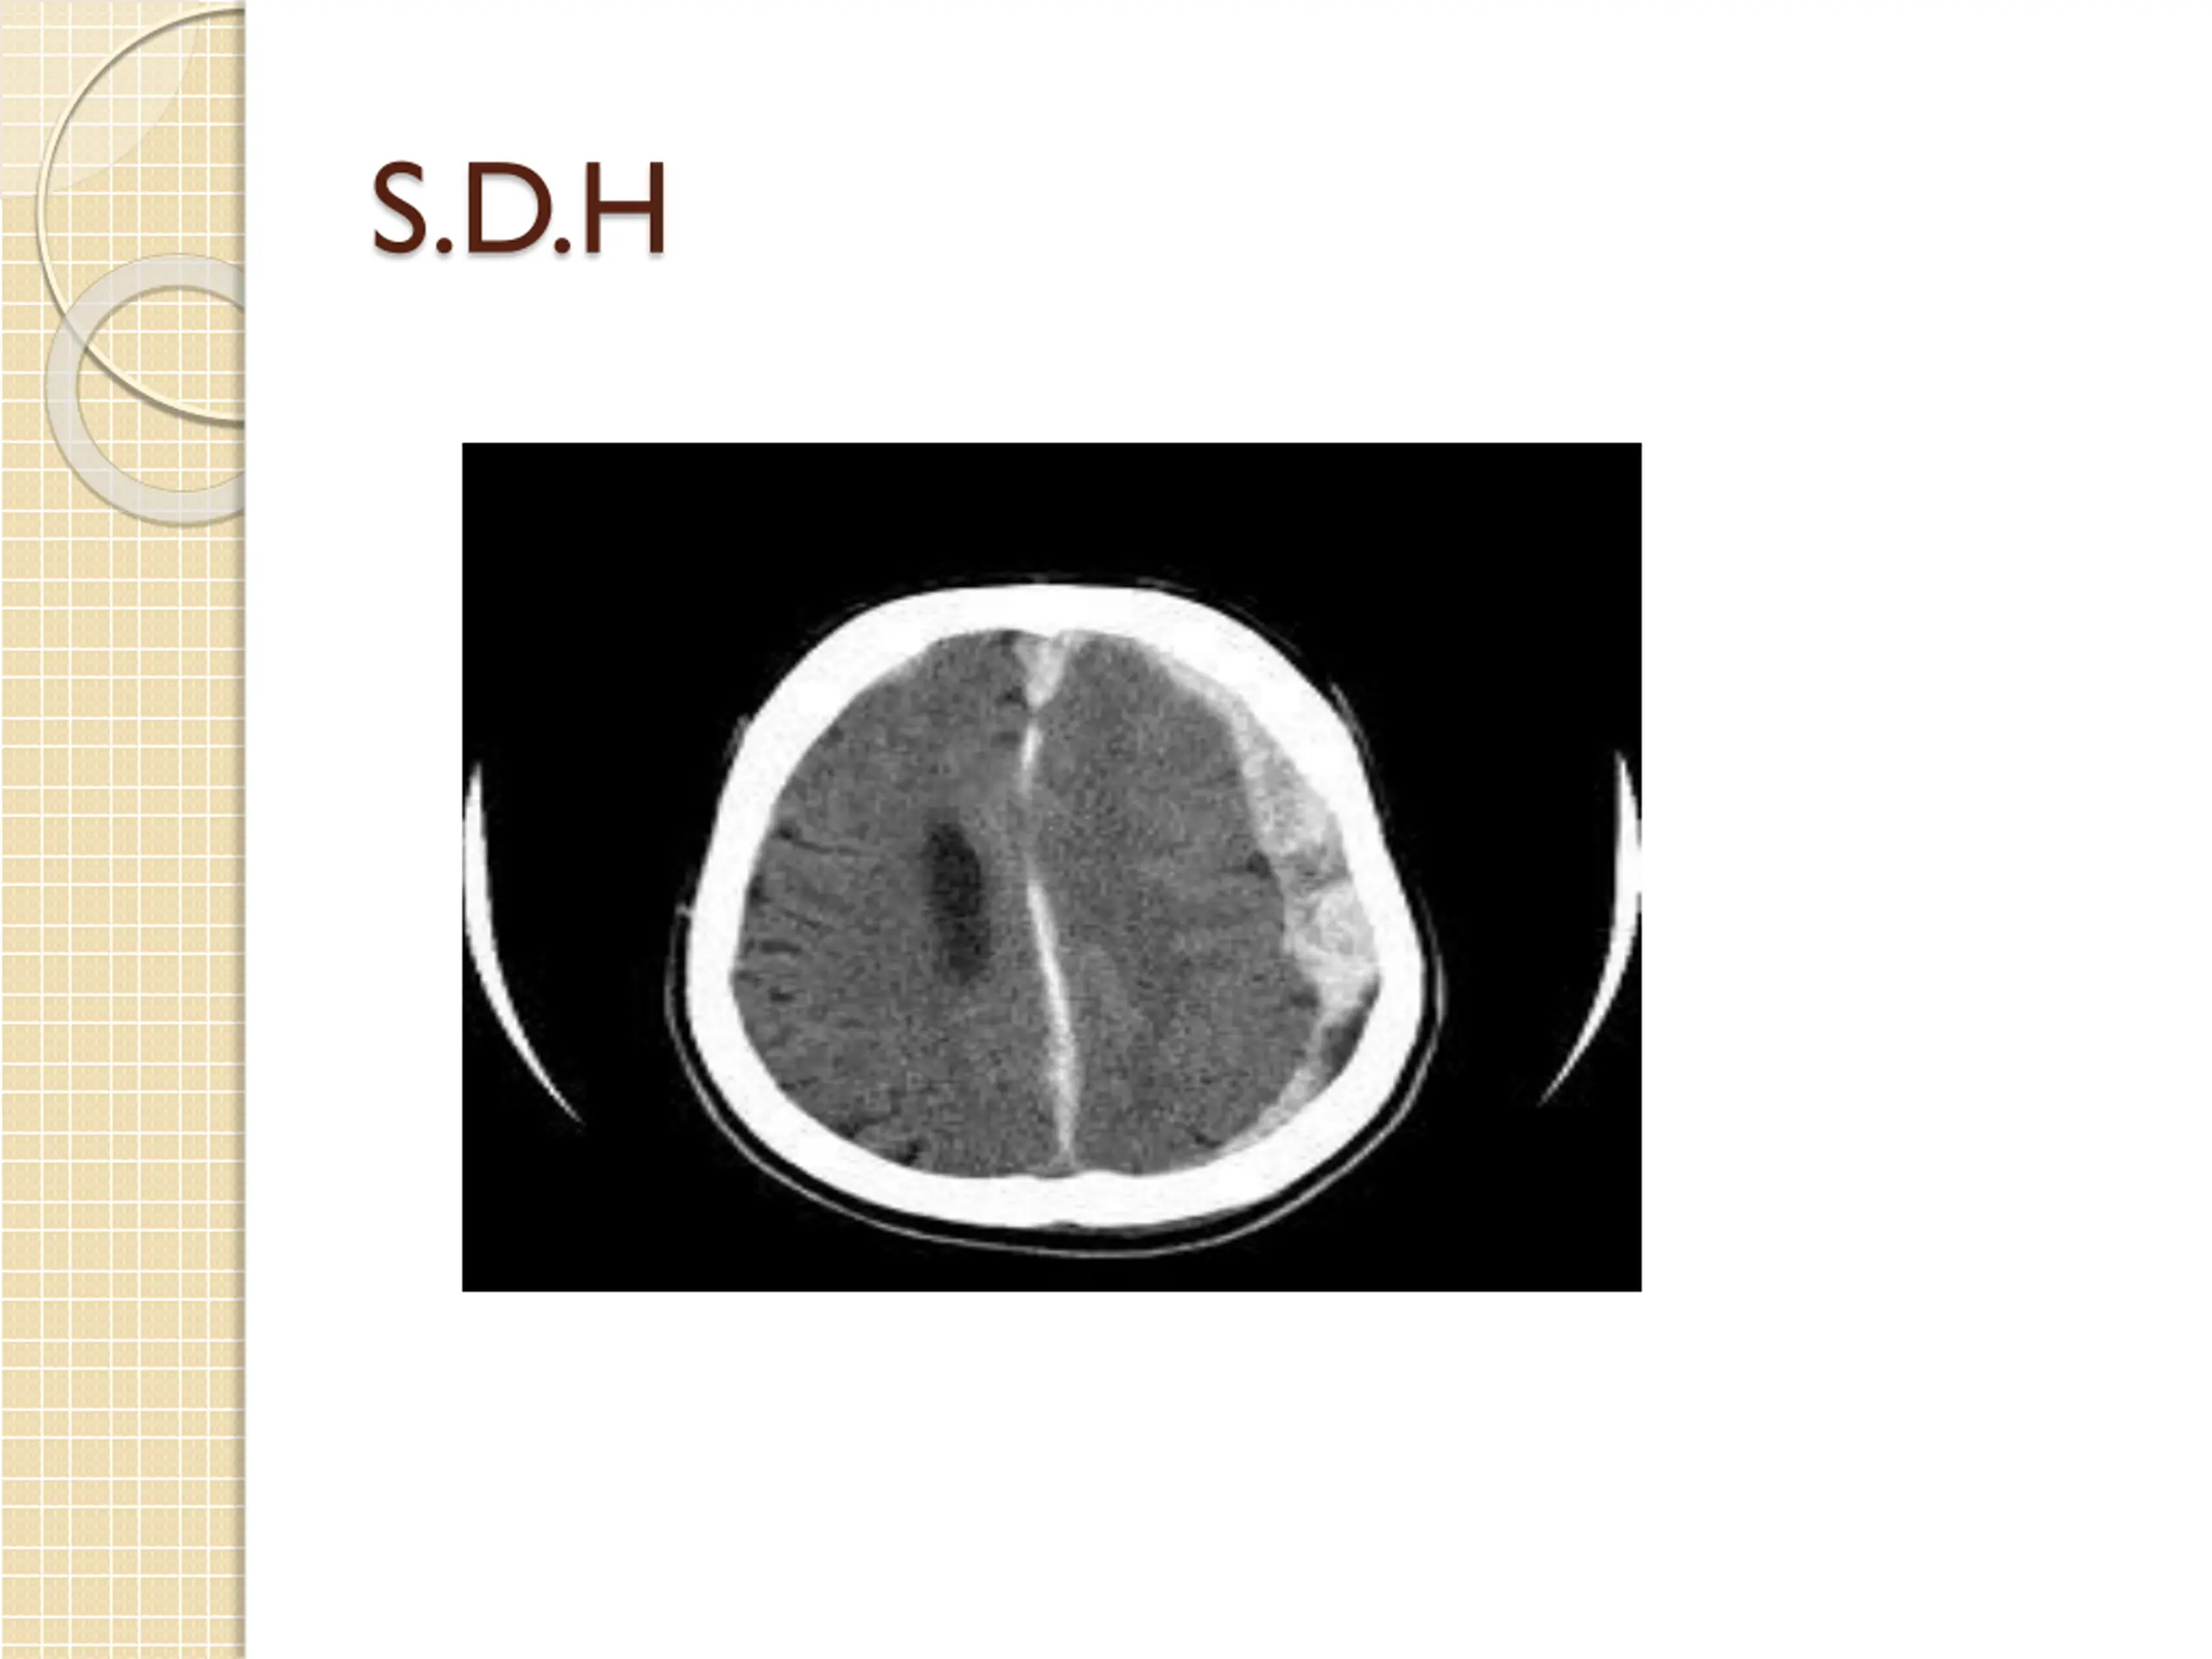

S.D.H : associated contusion and brain laceration result from contact or acceleration effect or result from torn cortical vessels especially in trivial head trauma in old age patients